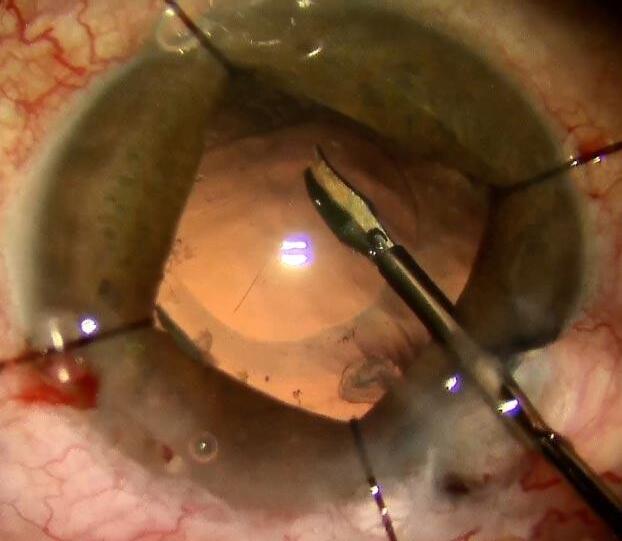

Una de las maniobras que nos ayudan a contener una RCP es la capsulorrexis posterior (Imagen 2)

Imagen 2.

El concepto principal a destacar a la hora de justificar esta maniobra es lograr la continuidad del borde de la capsulorrexis. Como bien sabemos por tratar con la cápsula anterior en cada cirugía de catarata convencional, la pérdida de la continuidad en la “rexis” es factor fundamental para que tengamos una “fuga”, es decir una extension radial en la apertura de la cápsula. Este concepto aplica de la misma manera a la cápsula posterior. Por lo cual, cuando tenemos una solución de continuidad en la cápsula posterior, cualquier maniobra que realicemos puede aumentar su tamaño. Desde la colocación de viscoelástico, vitrectomía anterior, colocación de la lente, hasta disbalances de presión entre el segmento anterior y segmento posterior.

Existen RCP que son evidentemente irregulares y con bordes discontinuos, pero también nos podemos encontrar con una apertura aparentemente circular (Imagen 3) , sobre todo cuando la rotura sucedió con súbitos colapsos en la cámara anterior y la cápsula entra en contacto brevemente con el tip del faco o de la bomba de aspiración. Incluso en esta situación no nos debemos fiar de la continuidad, ya que puede haber microdesgarros en el borde que extiendan la apertura en las maniobras subsiguientes.